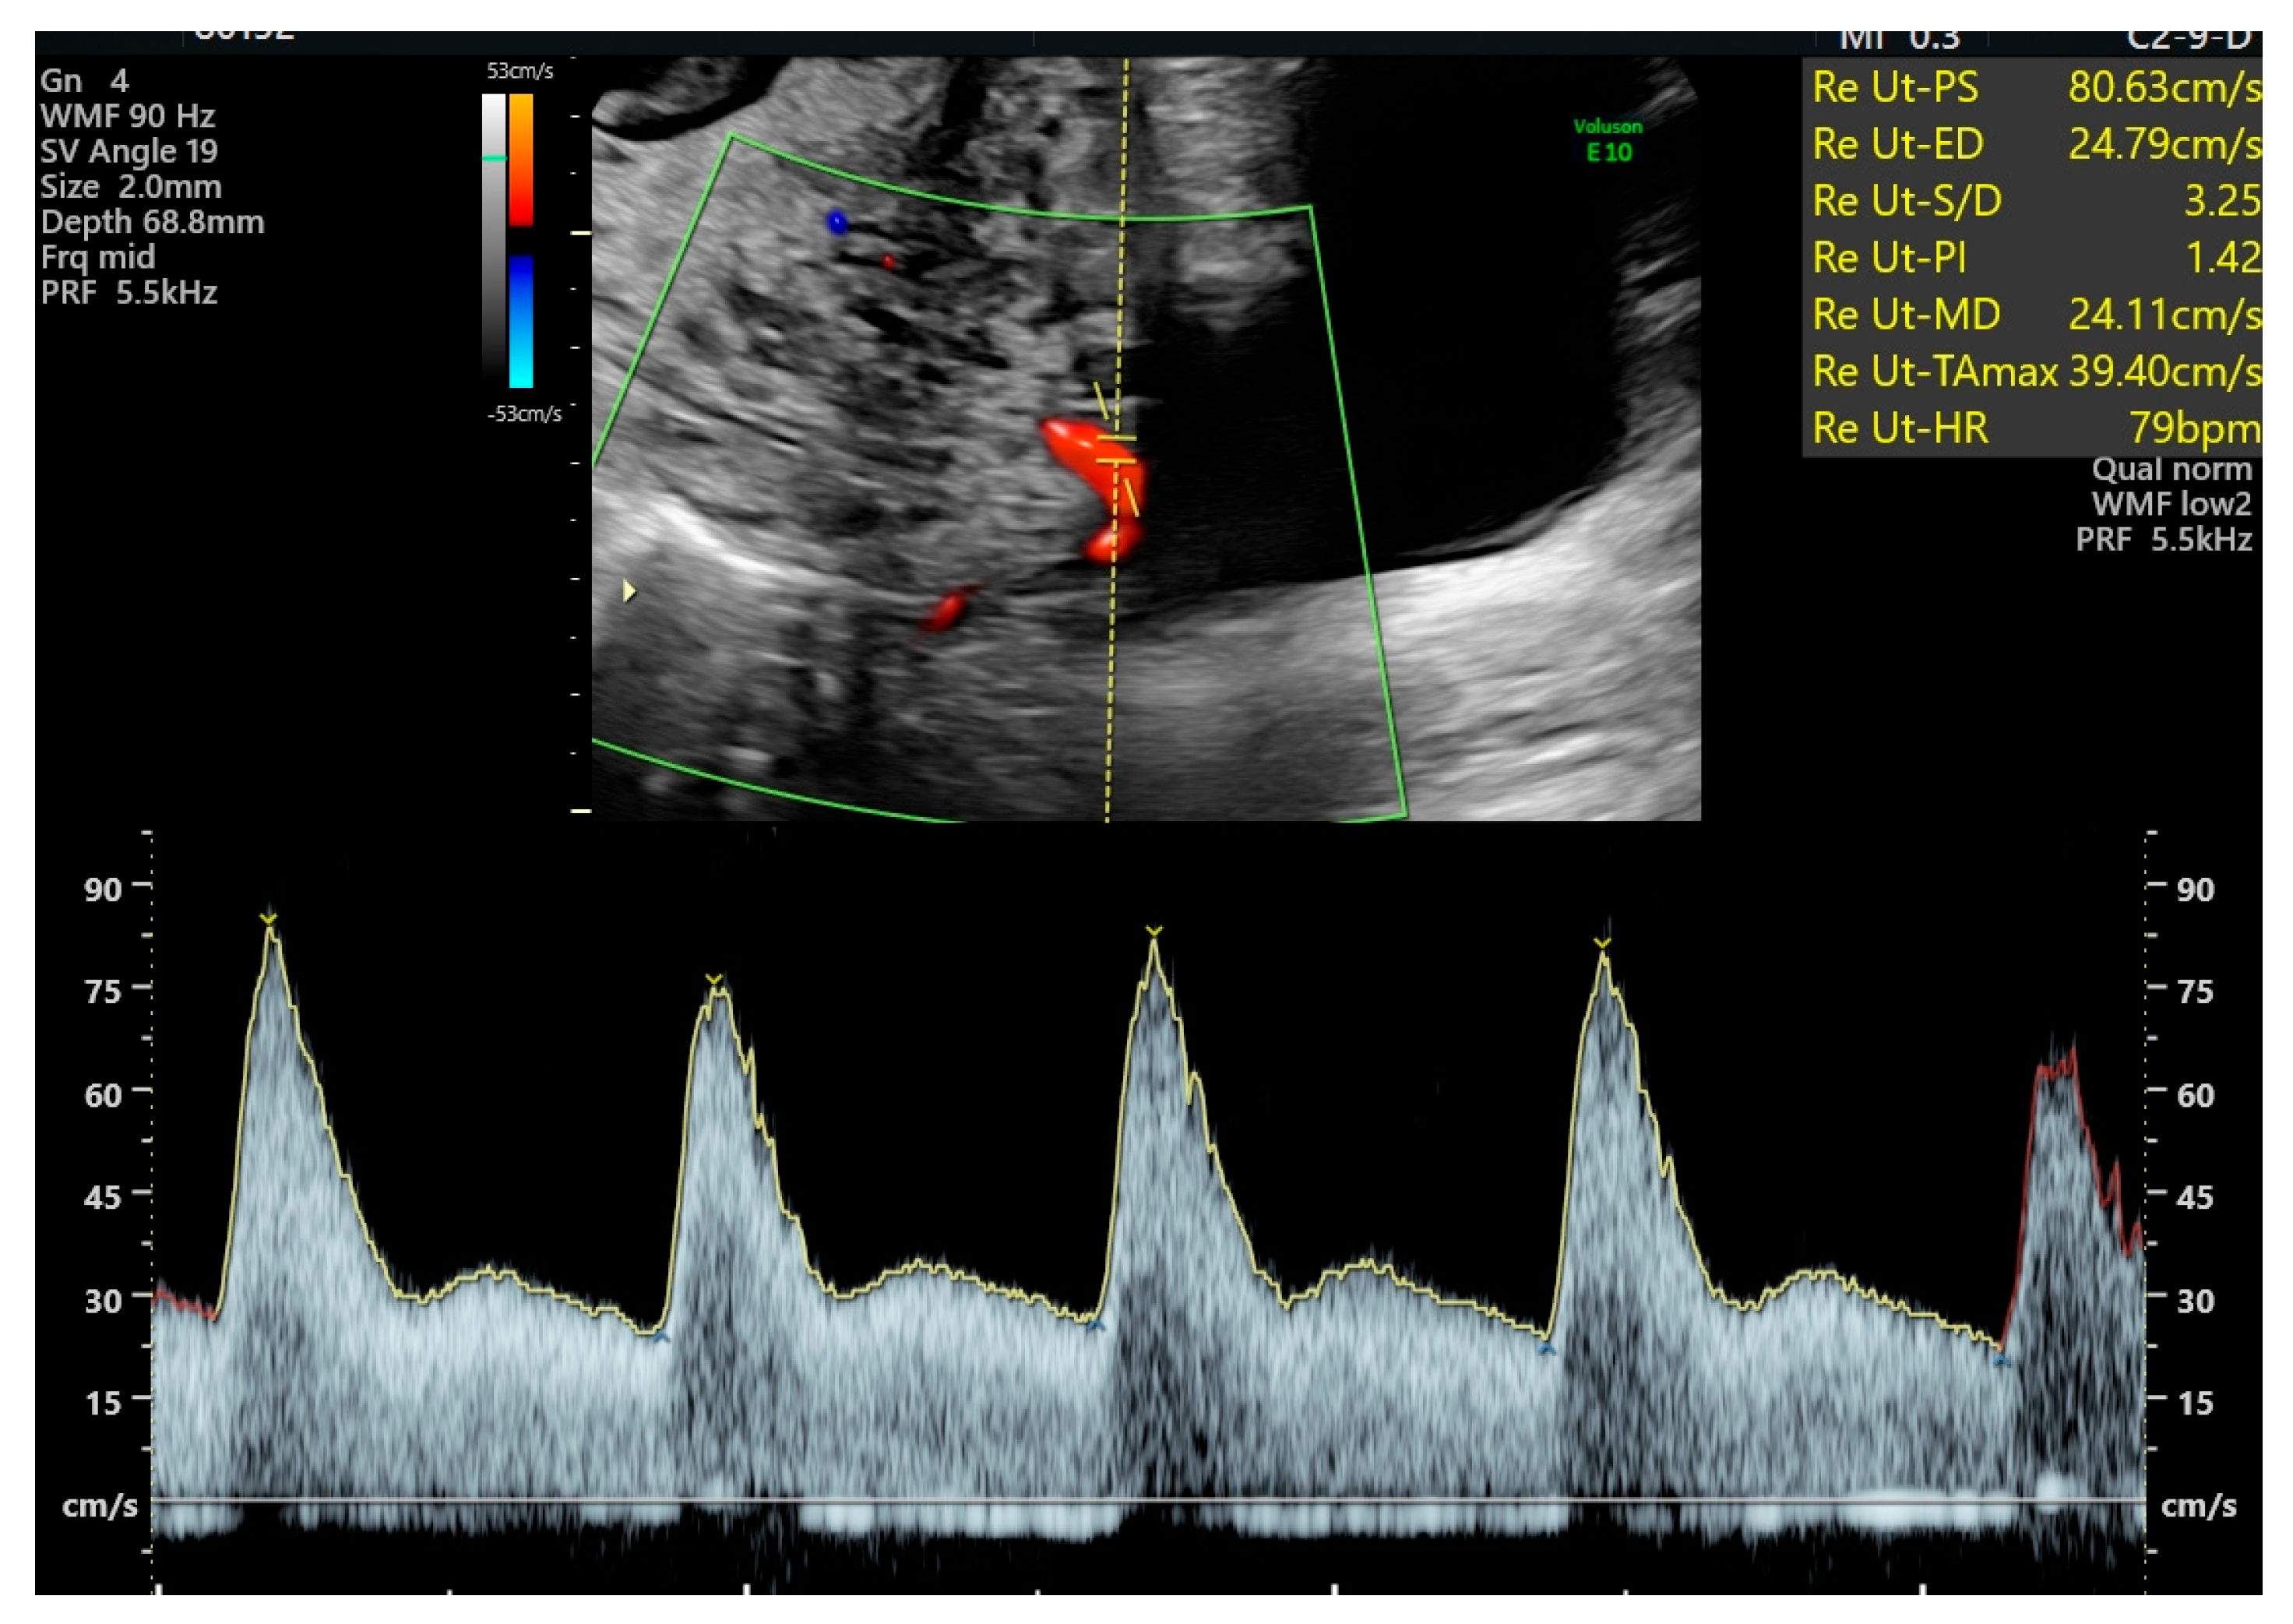

| Mean UtA-PI, * | 0.75 (0.64–0.91) | 0.74 (0.64–0.89) | 0.76 (0.64–0.93) | 0.8064 |

| Mean UtA-RI, * | 0.5 (0.45–0.55) | 0.48 (0.44–0.55) | 0.5 (0.42–0.56) | 0.8506 |

| Minimum UtA-PI, * | 0.65 (0.54–0.81) | 0.65 (0.59–0.81) | 0.66 (0.54–0.8) | 0.7384 |

| Maximum UtA-PI, * | 0.89 (0.7–1.01) | 0.89 (0.7–1.01) | 0.88 (0.7–1.01) | 0.7981 |

| Notching left UtA, † | 6 (6.2) | 3 (7.5) | 3 (5.3) | 0.8506 |

| Notching right UtA, † | 2 (2) | 0 (0) | 2 (3.5) | 0.3396 |

| Mean UtA-PI, * | 0.73 (0.65–0.88) | 0.81 (0.65— 0.94) | 0.2842 |

| Mean UtA-RI, * | 0.49 (0.45–0.53) | 0.52 (0.46–0.55) | 0.2958 |

| Minimum UtA-PI, * | 0.64 (0.53–0.74) | 0.7 (0.59–0.83) | 0.0511 |

| Maximum UtA-PI, * | 0.86 (0.73–1.01) | 0.9 (0.7–1.02) | 0.8160 |

| Notching left UtA, † | 2 (4.9) | 4 (7.4) | 0.6307 |

| Notching right UtA, † | 2 (4.9) | 0 (0) | 0.1102 |